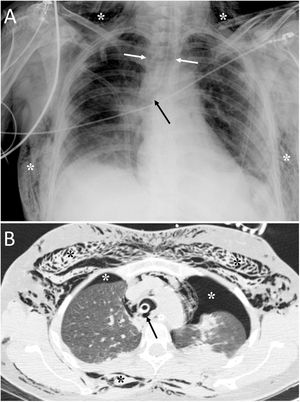

Tracheal rupture is rare, represents 15%–27% of all tracheobronchial lesions and is associated with high morbidity and mortality.7 The most common causes are chest trauma and orotracheal intubation (Fig. 2). Diagnosis can be delayed because the clinical and radiological findings are not specific, leading to complications such as failure of mechanical ventilation, mediastinitis, airway stenosis, bronchiectasis, recurrent infections and impaired lung function.7,8 Tracheal tears are frequently vertical and longitudinal and are located at the junction of the cartilaginous and membranous portions.8 The common and non-specific radiological findings are cervical subcutaneous emphysema and PM. If the cause is orotracheal intubation, a large dilatation and herniation of the endotracheal tube balloon outside the tracheal wall can be seen on computed tomography (CT) as a specific sign.7,8 Other signs would be the visualisation of the endotracheal tube outside the tracheal lumen, a focal defect in the tracheal wall and a deformity of the trachea.7 The CT enables the tracheal tear to be located in 70%–100% of cases, although the definitive diagnosis is made by bronchoscopy.8

A 36-year-old woman with attempted autolysis due to ingestion of benzodiazepines and acute respiratory failure, who presented with subcutaneous cervicofacial and thoracic emphysema after intubation. A) The chest X-ray revealed massive subcutaneous emphysema (white asterisks), hyperdistention of the endotracheal tube balloon (white arrows) and the distal end of the endotracheal tube in the proximal segment of the right main bronchus (black arrow). B) Computed tomography revealed pneumomediastinum with significant subcutaneous emphysema (black asterisks), bilateral pneumothorax (white asterisks) and hyperdistention of the endotracheal tube balloon with deformity of the posterior wall of the intrathoracic trachea (black arrow) due to post-intubation tracheal rupture. Treatment consisted of inserting two pleural drainage tubes for bilateral pneumothorax and selective intubation of the right main bronchus, with extubation at 36 h.